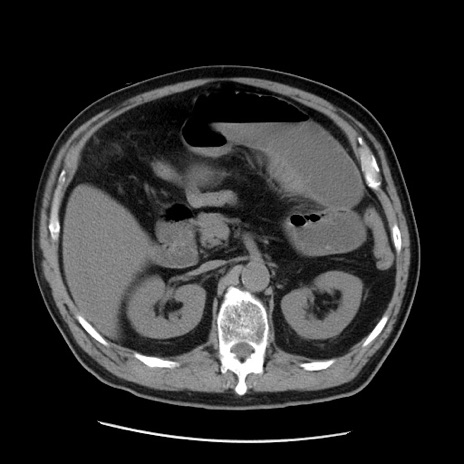

症例20(横断像)

【症例】 60歳代男性

【主訴】 腹部膨満、嘔吐

【現病歴】5日前頃より倦怠感を認め食事量減少し4日前の朝嘔吐、食事摂取困難となった。 3日前近医受診し点滴施行され整腸剤などを処方された。 当日他院を受診し、腹部膨満著明、炎症反応の上昇(CRP10.8、WBC11200)あり、紹介受診となる。

【身体所見】 意識JCS1 受け答えがはっきりしないBP 111/57mHg、 P 67bpm、、BT35.2°C、SpO2 97%(RA)、 腹部:膨隆、打診で鼓音あり、全体的に圧痛有り、腸蠕動音(-)、反跳痛ははっきりせず。

【データ】WBC 11400、CRP 14.20